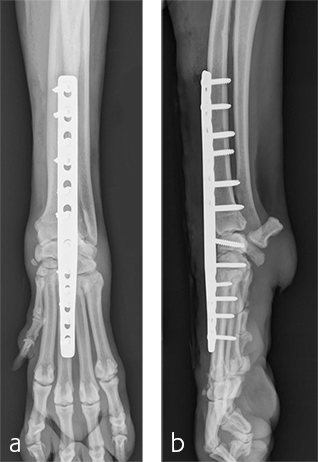

Immediate postoperative images confirmed anatomic alignment and adequate carpal extension (Fig 10). At the 11-week postoperative follow-up examination, functional recovery was very good with images revealing stable implants and healing of the arthrodesis (Fig 11). The dog was then allowed to return to normal activity.